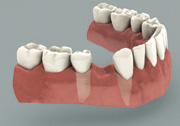

Untreated Missing Tooth

Losing one or more of your teeth starts a chain of events that can have dire physical and cosmetic consequences. The most obvious result is a gap in your smile. Less obvious is the loss of chewing function and the inability to eat a complete diet that can result from tooth loss. While these are certainly serious issues, a potentially bigger problem lies hidden beneath the surface: bone loss.

Your jawbone needs the chewing action of the teeth to stimulate it and keep it strong. Otherwise it will begin to disappear (atrophy) in the same manner that the unused muscles beneath a cast supporting a broken bone get smaller. Without the support of your teeth and facial bones, your face will begin to look prematurely aged. The good news is that tooth replacement with dental implants offers a solution to help prevent bone loss..